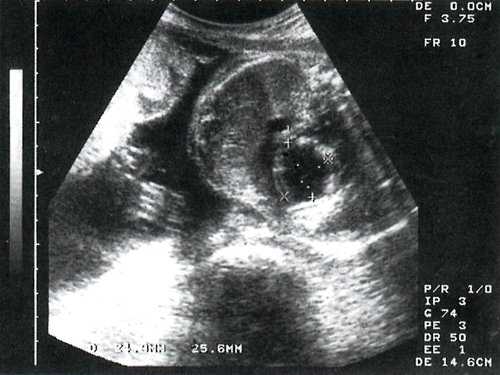

При скрининговом исследовании в 3 наблюдениях у молодых первобеременных при минимальном сроке гестации 24 недели выявлены одинаковые изменения сердца плода. Отмечалось значительное увеличение размеров сердца за счет левого желудочка с шарообразной его конфигурацией. Верхушка сердца полностью сформирована левым желудочком. Миокард левого желудочка утолщен и полость сферически расширена, при этом межжелудочковая перегородка выпячивается в полость правого желудочка (рис. 1).

Рис. 1. Эндокардиальный фиброэластоз у плода в 26 недель гестации. Четырехкамерное сечение сердца плода.

Безусловно, антенатальная диагностика фиброэластоза основывается в значительной степени на нарушении сократимости миокарда и плотности эндокарда. По нашим данным, наиболее характерным является плотность эндокарда, достигающая нескольких миллиметров, эхопозитивность структуры эндокарда и "светящийся" эндокард (см. рис. 1). В зависимости от формы полость может быть расширена и представлять классический вариант патологии - неподвижные стенки, блестящий плотный эндокард и выпячивание межжелудочковой перегородки в сторону правого желудочка, т.е. шарообразная форма левого желудочка.